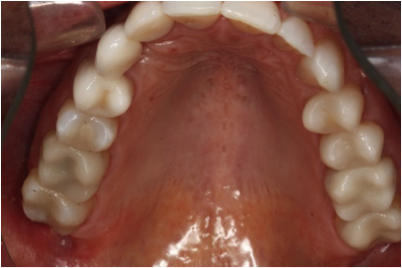

This patient desired to maintain the position and shape of all of his teeth. He opted for CEREC® copy-milled restorations on most of his back teeth. Note how the shape mimics precisely the original shape of his teeth that had multiple large and failing fillings. He is very pleased with the result and has remarked on several occasions how comfortable his new restorations feel.